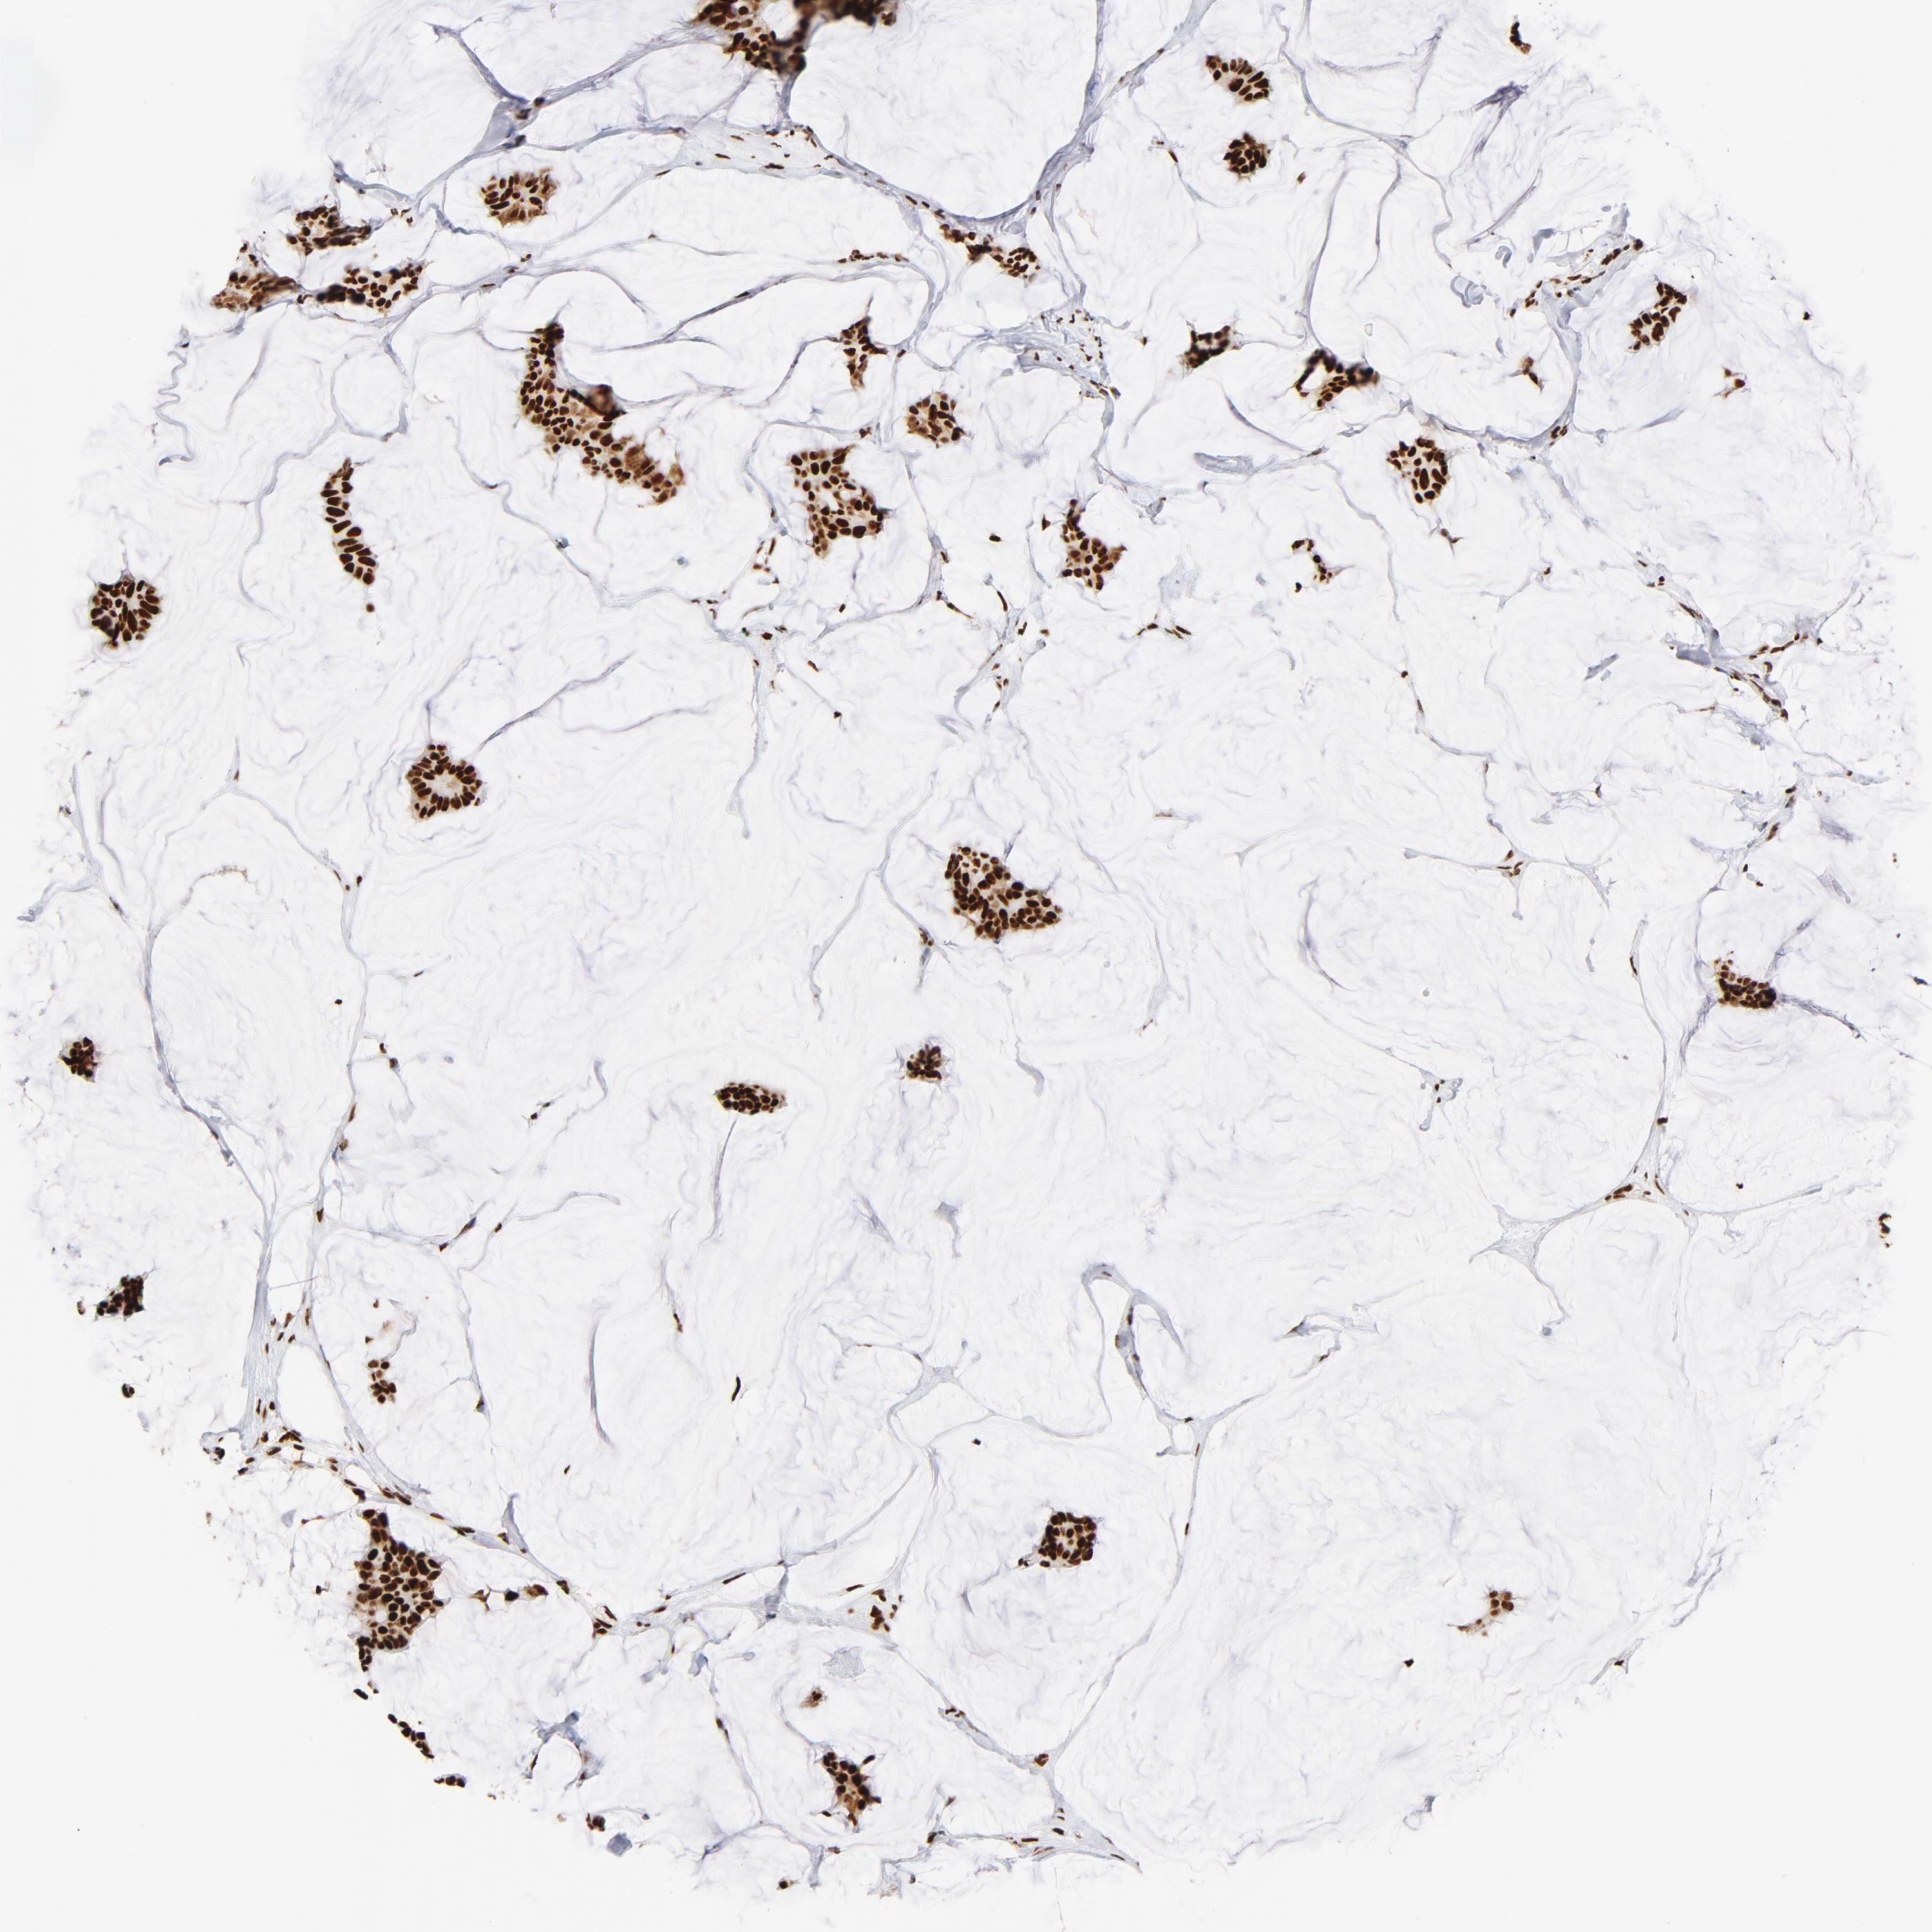

BRCA TCGA BRCA VALIDATION PROTEIN EXPRESSION